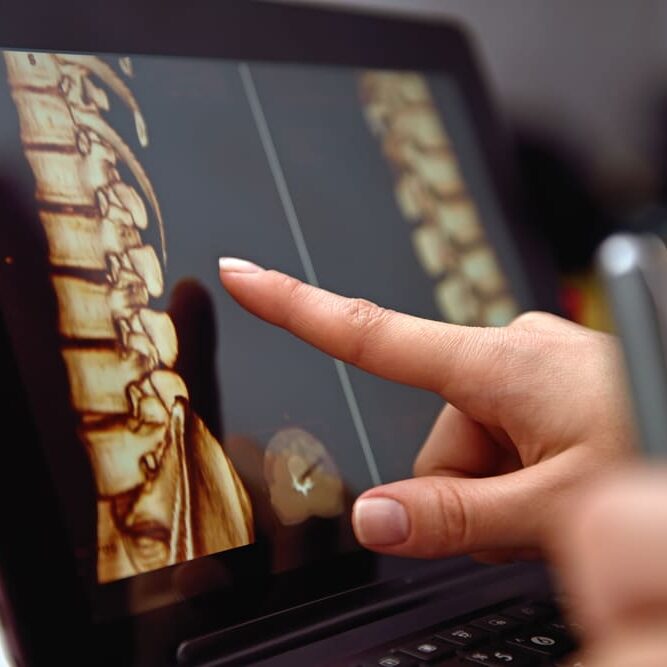

Le patient se présentera à cette première séance muni des imageries de sa colonne vertébrale.